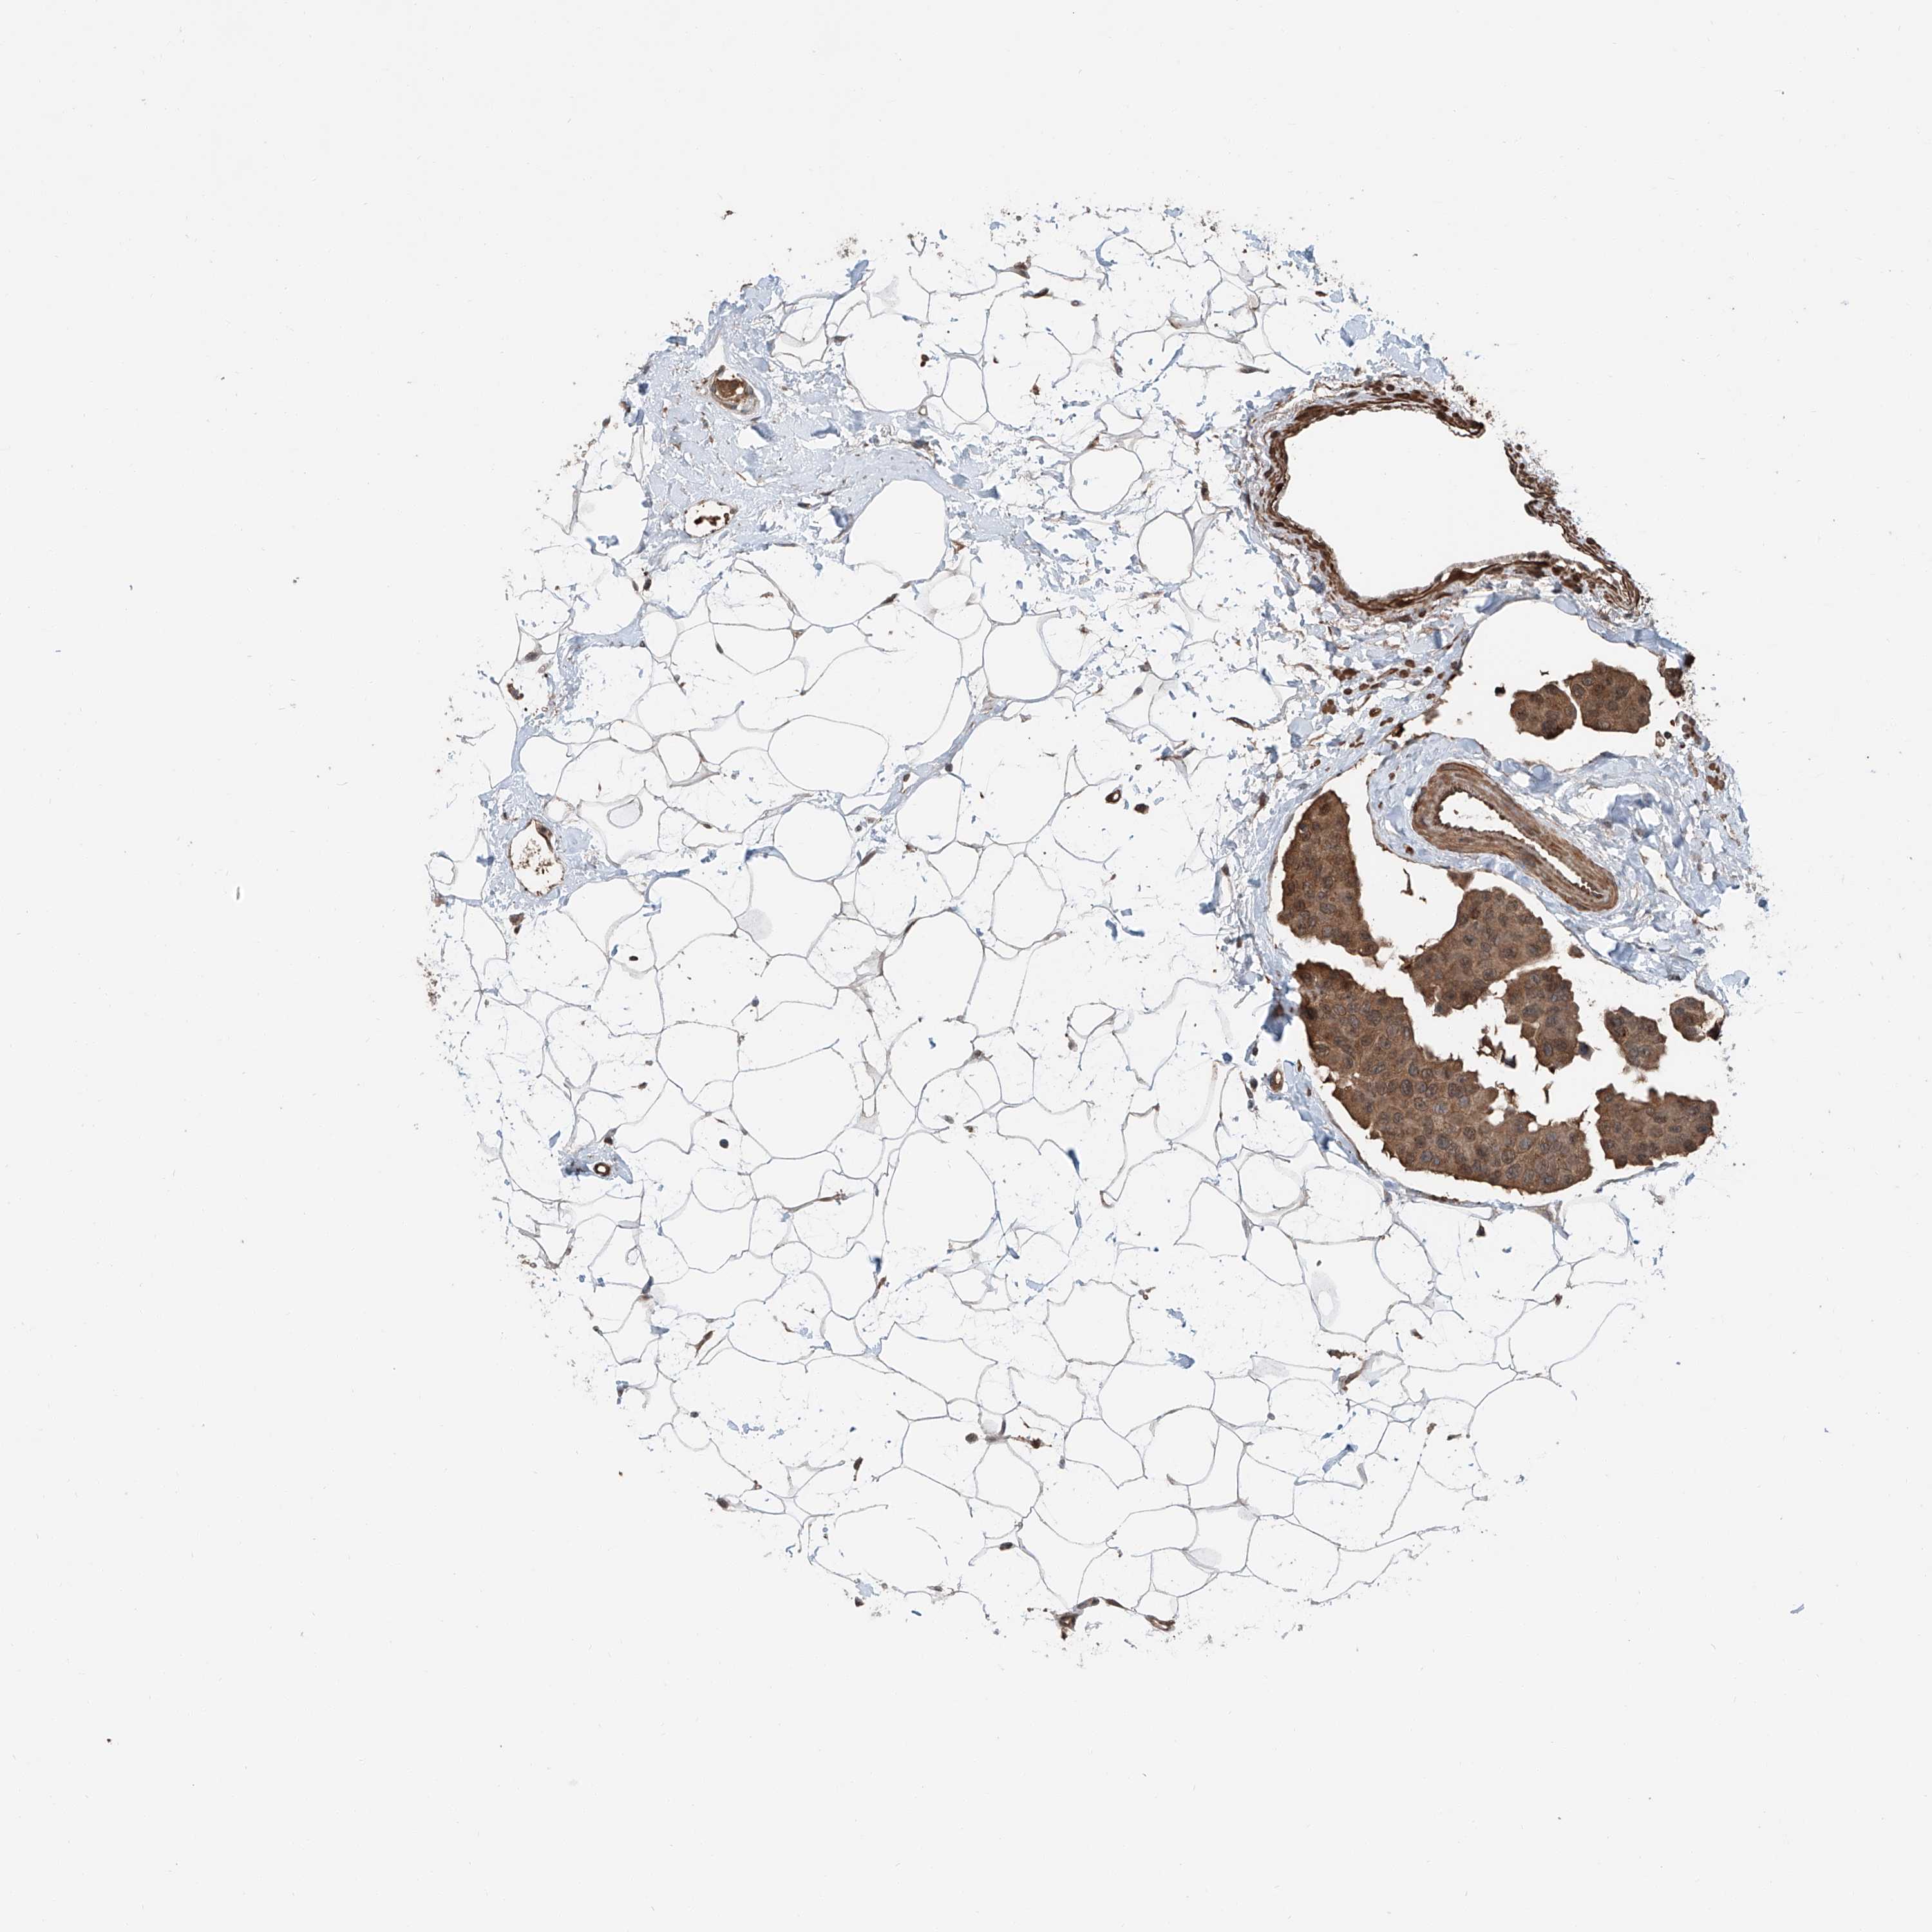

CANCER BREAST CANCER Show tissue menu

BRCA TCGA BRCA VALIDATION PROTEIN EXPRESSION